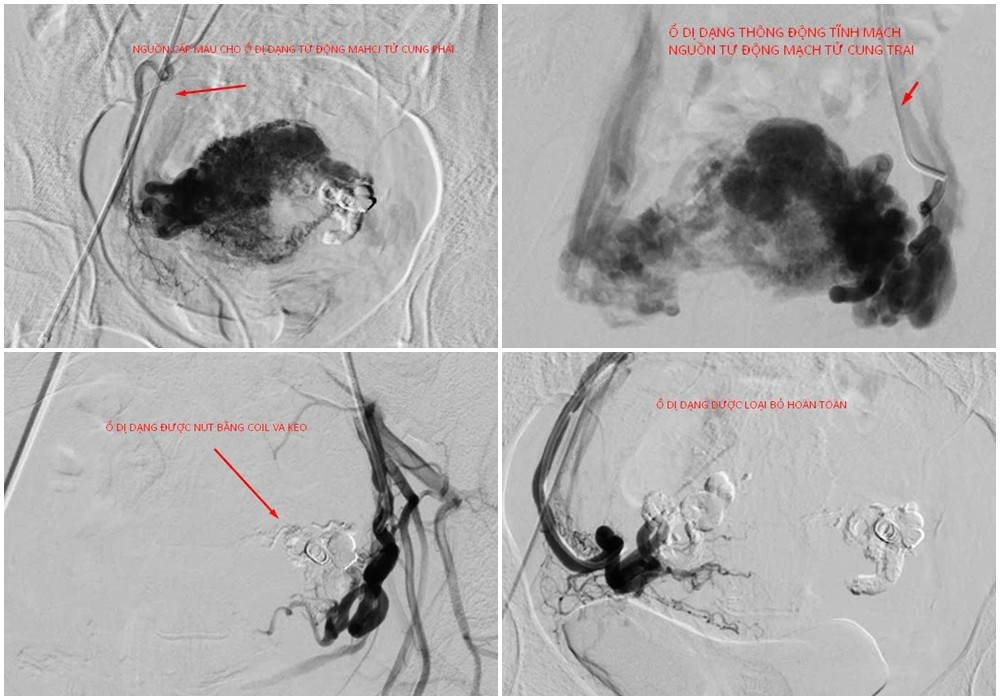

Dưới hướng dẫn của hệ thống chụp mạch xóa nền 2 bình diện DSA, các bác sĩ luồn ống thông chuyên dụng đến vị trí ổ dị dạng và tiến hành nút mạch bằng keo sinh học và coil. Kiểm tra thấy các nhánh động mạch tử cung hai bên cấp máu cho ổ thông động tĩnh mạch đã được nút tắc hoàn toàn và triệt để.

Hình ảnh ổ thông động tĩnh mạch tử cung với nguồn cấp máu phức tạp được kíp can thiệp nút mạch loại bỏ hoàn toàn - Ảnh BVCC

BS.CKII Ngô Quang Chức cho biết: “Trường hợp bệnh nhân H. phát hiện ổ thông động tĩnh mạch có nhiều nguồn cấp máu phức tạp, nguy cơ lớn nhất là xuất huyết ồ ạt, thậm chí có thể gây sốc mất máu, đe dọa tính mạng.

Can thiệp nút mạch là lựa chọn ưu tiên trong những trường hợp như vậy, bởi hiệu quả cầm máu tức thì, ít xâm lấn, thời gian hồi phục nhanh và đặc biệt là bảo tồn tử cung, không ảnh hưởng đến khả năng sinh sản.